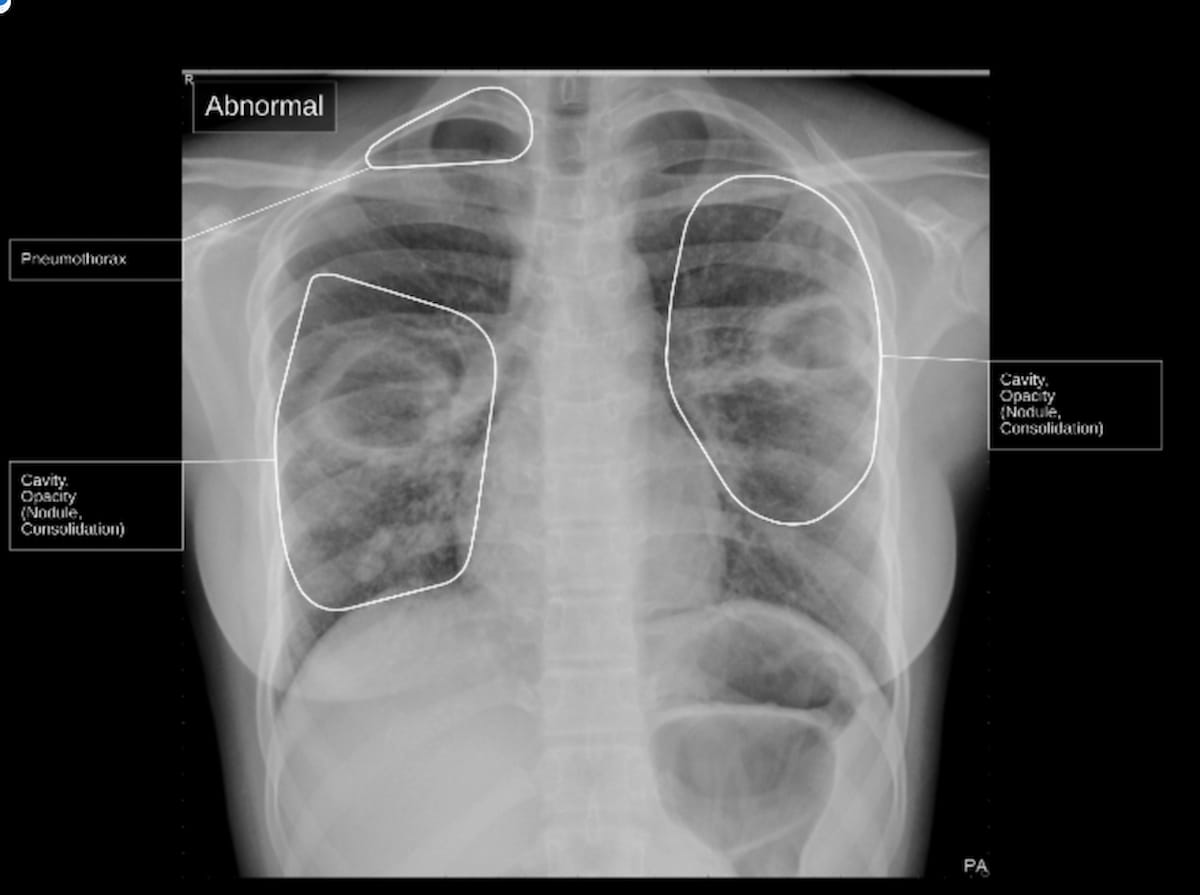

The qSpot-TB device, which recently garnered a breakthrough device designation from the FDA, localizes signs of TB on chest X-rays, and provides a conclusion of whether TB is present or not, according to Qure.ai, the developer of qSpot-TB. (Image courtesy of Qure.ai)

Qure.ai, the developer of qSpot-TB, said the device localizes signs of TB on chest X-rays and provides a conclusion of whether TB is present or not.